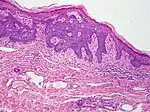

| Morpheaform basal-cell carcinoma (also known as "cicatricial basal-cell carcinoma", and "morphoeic basal-cell carcinoma") | Narrow strands and nests of basaloid cells, surrounded by dense sclerotic stroma.[31] | Aggressive[28]: 748 [29]: 647 |  |

| Infiltrative basal-cell carcinoma | Deep infiltration.[29]: 647 | Aggressive[29]: 647 | |